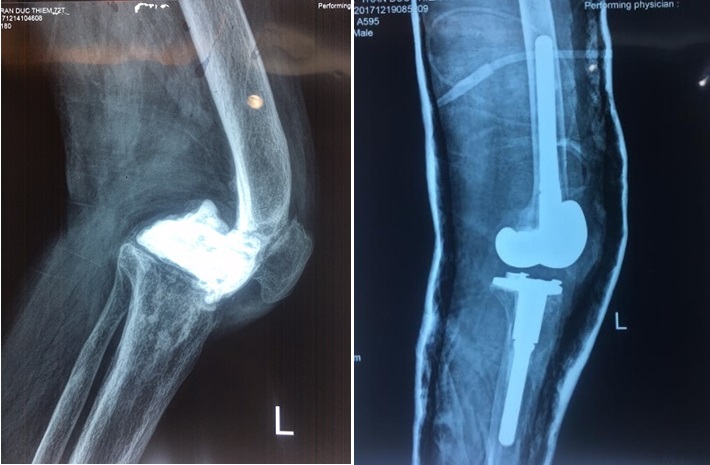

Ung thư xương thường gặp ở gần gối, xa khuỷu, nghĩa là hay gặp ở đầu trên xương chày, đầu dưới xương đùi (gần gối), đầu trên xương cánh tay, đầu dưới xương quay (xa khuỷu tay).

Sau một thời gian sử dụng, nhiều bệnh nhân đã từng được thay khớp gối nhân tạo gặp vấn đề về khớp và phải tìm đến bác sĩ để thay lại khớp gối nhân tạo lần 2. Các bác sĩ Khoa Chấn thương Chỉnh hình 1, Bệnh viện Việt Đức lần đầu tiên tiến hành thay lại khớp gối lần 2 cho bệnh nhân, giải thoát cho người bệnh khỏi những cơn đau sau một thời gian thay khớp gối lần đầu.